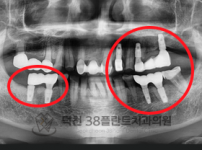

치료전후